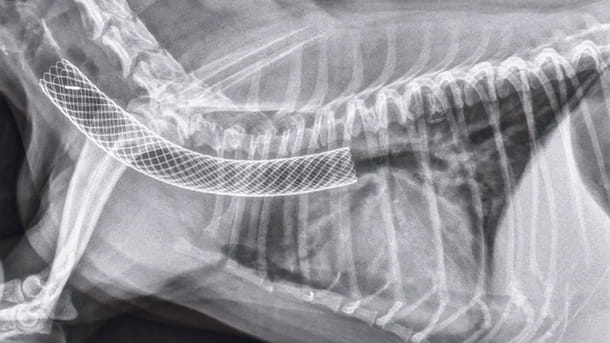

Tracheal stent